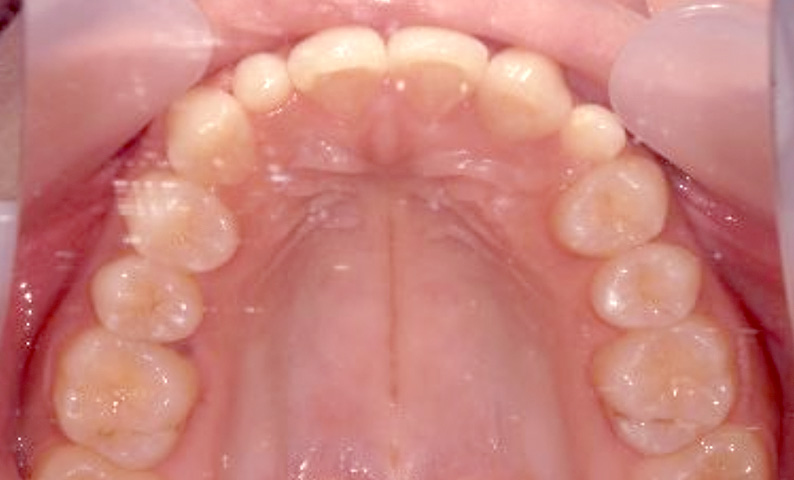

症例_025 上下顎の部分矯正

治療期間:13ヶ月金額:51万円+税女性前歯のガタガタ出っ歯

| Before | After |

|---|---|

|